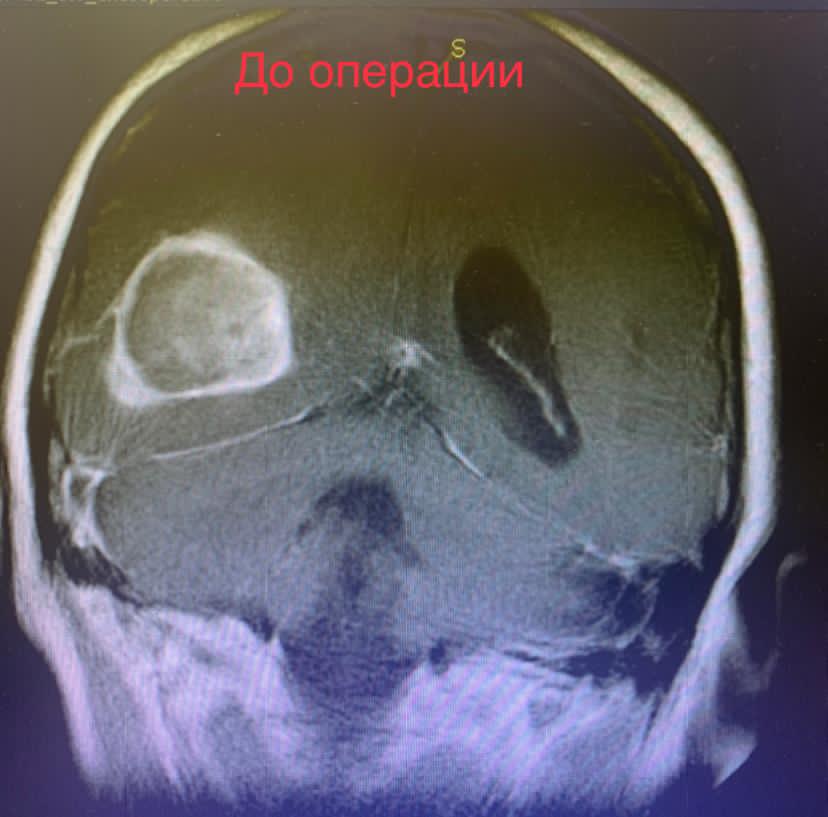

Проведены дополнительные обследования. МРТ головного мозга выявила опухоль головного мозга размером 3х4х4 см, с большим перифокальным отеком и смещением срединных структур головного мозга, что требовало неотложного нейрохирургического вмешательства.

Выполнено микрохирургическое удаление опухоли единым блоком.